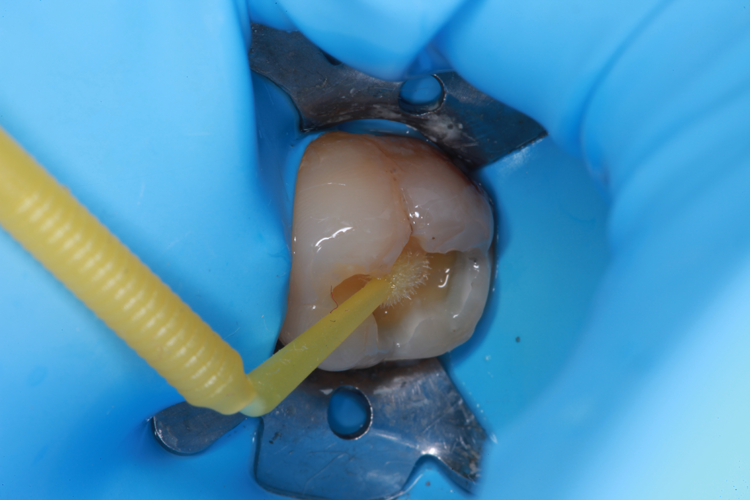

The enamel was etched for 20 seconds with Select HV from BISCO (Fig. 3), and ALL-BOND UNIVERSAL (BISCO) was applied (Fig. 4).

Fig. 3: Enamel etched for 20 seconds with Select HV. Fig. 4: ALL-BOND UNIVERSAL applied.